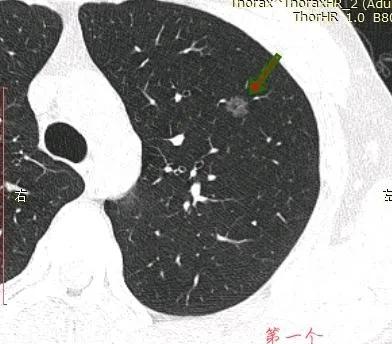

这位云南的小伙子,21岁,因为发烧查出4个磨玻璃肺结节,贴吧向我求助后,我断定大的9mm磨玻璃结节结节已有危险,因为是初次发现,但还是要求按指南先随访排除炎症,哪怕10%的炎症或消掉的机会也不能放过。

因为患者有肺癌家族史,对肺癌恐惧极深,这种亲历的梦魇般的恐惧,站在岸上的其他人没办法理解。虽然在网上已咨询几次,但患者还是直接千里迢迢从云南跑过来找我面诊,希望得到一个更确定的诊断结果。仔细看了他带来的资料,我确定左肺9mm的结节已是微浸润腺癌,需要手术切除,但还是劝返,和言劝其先随访排除炎症,保证不耽误病情。

在11月16号,自己担心去了一趟胸外科门诊,医生看了片子之后直接让我复查胸部平扫➕HRCT,看了复查片子之后医生问过我也没有家族史,随后医生说癌症可能性非常大,并且已经说到要手术和靶向药治疗。但还是让我吃半个月莫西沙星,由于当地拜复乐没买到,就吃了其他牌子的莫西沙西,最后网购吃了三颗拜复乐!距离复查只有一周,这个月以来一直焦虑。因为双肺足足有四个磨玻璃结节,在网上看到戴主任的专业,希望能够得到戴主任的建议,4个结节冷月都帮我截图了,我放在下面,麻烦戴主任帮我看看!

左肺的,已有事。右肺,没啥事。